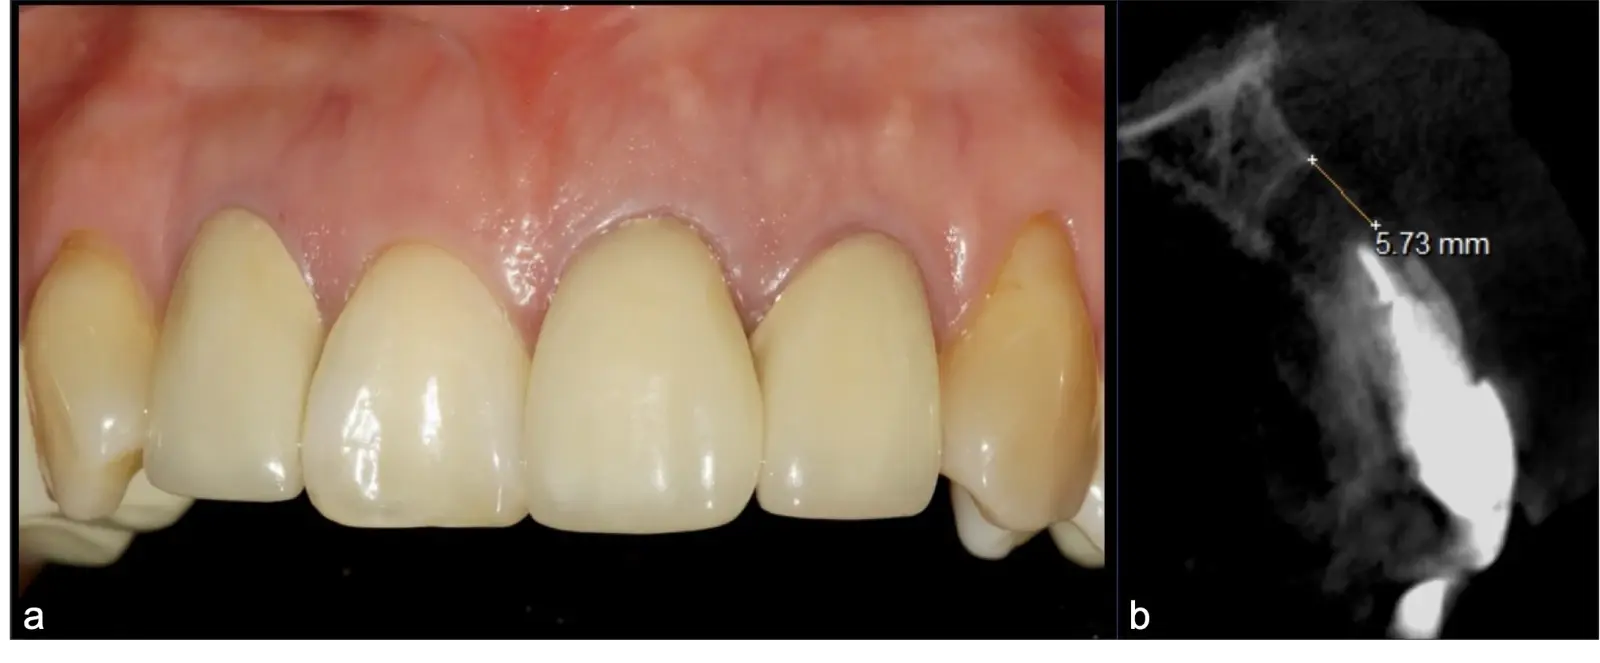

La microcirugía endodóntica apical busca conservar la mayor cantidad de longitud de raíz y de hueso circundante sano para no afectar la estabilidad de la pieza.11 Por ello, es ideal el uso de microscopios, elementos de magnificación, instrumental específico (insertos de ultrasonido endodónticos) y materiales de sellado eficientes para el tratamiento retrogrado. Su éxito es alto y evidencia una cicatrización ósea completa en el 74% de los casos al año de tratamiento.12 Cabe destacar que este logro está asociado también, a predictores propios de cada paciente, como la edad, tipo de pieza, profundidad de sondaje y extensión de la lesión.1 El uso complementario de la tomografía computarizada es resaltante como el instrumento imagenológico de elección para la etapa de planificación microquirúrgica,13 ya sea para una ejecución a mano alzada o con guías prefabricadas.14,15

Para la obturación retrograda, el sellador más usado es el agregado de trióxido mineral (MTA)21 por sus propiedades hidrofílicas y de biocompatibilidad que favorece la neoformación ósea.3 Luego de la desinfección y secado, se realiza la obturación-compactación de rutina y se culmina con la reposición de los tejidos gingivales a través de puntos de sutura (Figura 10).